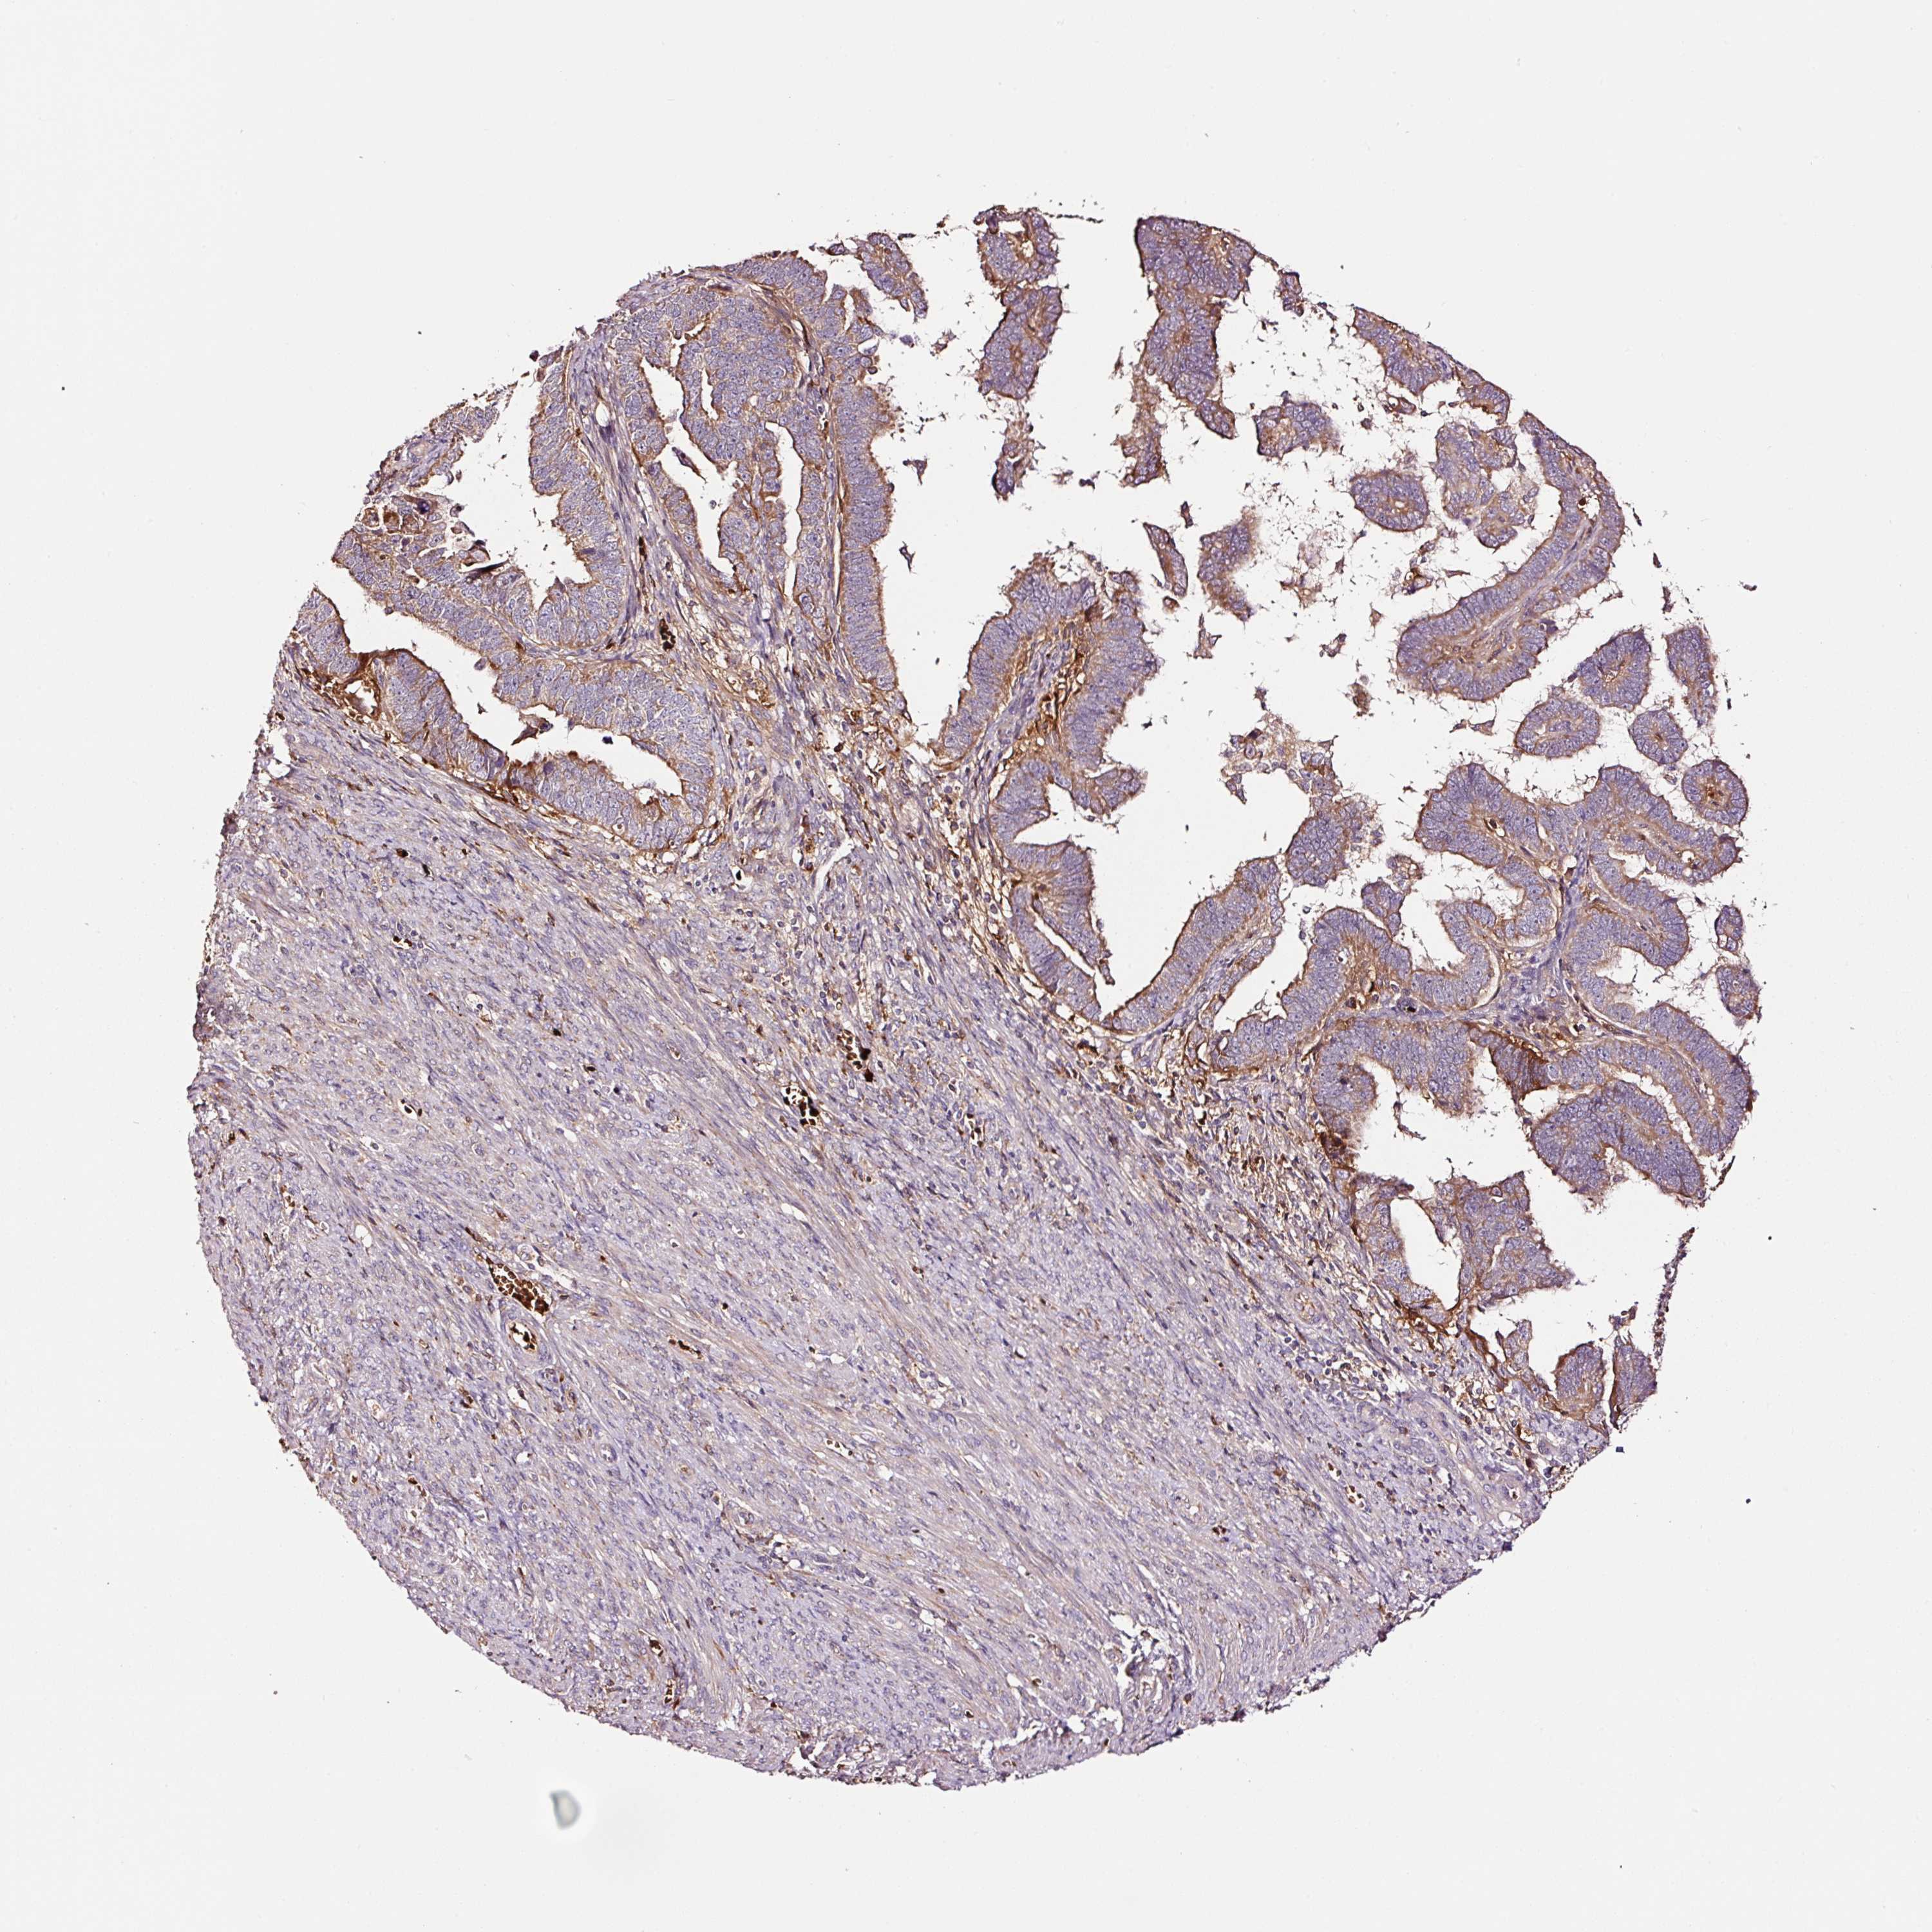

ENDOMETRIAL CANCER - Protein expressioni

A mouse-over function shows sample information and annotation data. Click on an image to view it in a full screen mode. Samples can be filtered based on level of antibody staining by selecting one or several of the following categories: high, medium, low and not detected. The assay and annotation is described here.

Note that samples used for immunohistochemistry by the Human Protein Atlas do not correspond to samples in the TCGA dataset.

Antibody stainingi

Antibody staining in the annotated cell types in the current human tissue is reported as not detected, low, medium, or high, based on conventional immunohistochemistry profiling in selected tissues. This score is based on the combination of the staining intensity and fraction of stained cells.

Each image is clickable and will lead to virtual microscopy that enables deeper exploration of all samples and also displays staining intensity scores, fraction scores and subcellular localization as well as patient and tissue information for each sample.

Antibody HPA046311

Antibody CAB033468

Staining

High

Medium

Low

Not detected

Intensity

Strong

Moderate

Weak

Negative

Quantity

>75%

75%-25%

<25%

None

Location

Nuclear

Cytoplasmic/membranous

Cytoplasmic/membranous,nuclear

Adenocarcinoma, NOS